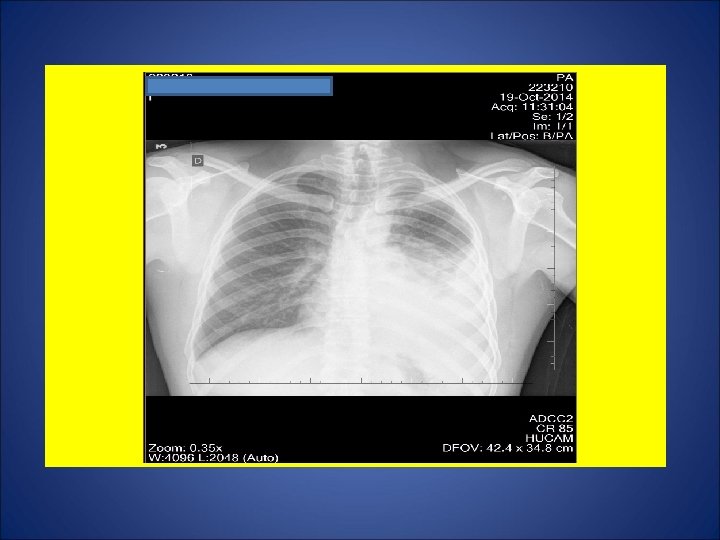

CASO 4, masculino, 30 anos, natural de Vitoria (ES), residente na Serra (ES), pedreiro. Há 2 meses e meio, tosse não produtiva, sudorese noturna, calafrios, adinamia. Surgimento de febre 20 dias e de expectoração purulenta 15 dias após. Episódios de escarros hemoptóicos 10 dias atrás e em 18 Out. Há 1 mês, dor em hemitórax esquerdo agravada com a tosse. Há 20 dias, dispnéia aos médios esforços. Durante os últimos 15 dias, perda de 10 Kg. Negou contato com casos de tuberculose. Negou tuberculose prévia. Negou tabagismo e etilismo. HIV negativo. Ex. fisico: P=73 Kg, Altura= 1, 63 m, IMC= 27, 5 Kg/m 2 (discreto sobrepeso), FC = 110 bpm. Marca de BCG em MSD.

ESCARROS ESPONT NEOS: 1º) 20/10/14: 10 m. L – PURULENTO - 30 min: BAC NEG - TRM: M. tuberculosis NÃO DETECTADO – CULT em curso 2º) 20/10/14: 10 m. L – MUCOPURULENTO – 30 min: BAC NEG – CULT em curso 3º) 21/10/14: 10 m. L – MUCÓIDE – 30 min: BAC NEG – CULT em curso